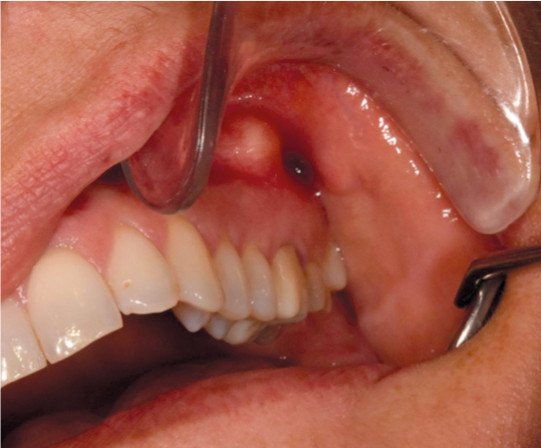

Tilstanden er oftest asymptomatisk. Dersom det tilkommer produksjon av puss, vil det dannes en periapikal abscess (figur 1). Tilstanden gir som regel hevelse, smerte og i varierende grad feber. Periapikale infeksjoner kan også spres til omkringliggende strukturer (figur 2). Hvis pusset dreneres via en fistel (ekstra- eller intraoralt), vil symptomene avta. Akutte periapikale abscesser må raskt dreneres for puss, enten via rotkanal eller ved incisjon. Det er primært tannleger som foretar behandlingen.

Perikoronitt er en infeksjon som oppstår i bløtvevet rundt delvis retinerte tenner (tenner som blir liggende i kjeven). Tilstanden oppstår i all hovedsak i tidlig voksen alder ved visdomstenner i underkjeven når matrester og andre fremmedlegemer samler seg mellom tannkjøttet og den delvis frembrudte kronen til tannen. Som oftest fører dette til en lavgradig, residiverende infeksjon med smerter, hevelse og rødme i omkringliggende gingiva. I noen tilfeller kan pasientene også ha trismus (kjevesperre), feber og nedsatt allmenntilstand.

Predisponerende faktorer er stress, menstruasjon og nylig gjennomgått/pågående annen sykdom. Perikoronitt er som regel selvbegrensende, men residiv er vanlig frem til tannen er frembrudt eller ekstrahert. I visse tilfeller kan det også tilkomme abscedering som krever incisjon og drenasje. Tenner med residiverende periokoronitt bør vanligvis ekstraheres i en rolig fase.